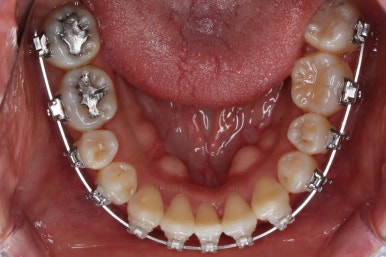

부분적으로 장치 셋팅을 다시 해줬고요.

밀고 당기기를 위해서 미니스크류를 셋팅했고요.

교합과 중앙선 및 디테일을 맞춰 나갑니다.